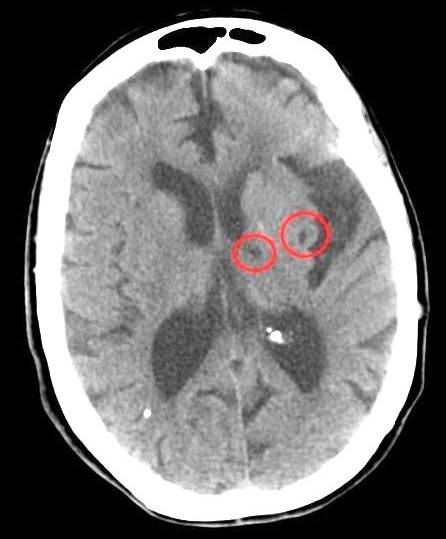

Lacunair infarct

Het woord 'lacunair' verwijst naar de kleine beschadigingen die een doorsnede hebben van 1 tot 15 millimeter die 'lacunes' wordt genoemd. Het lijken kleine gaatjes in de diepere hersengebieden, bijvoorbeeld de gebieden van de hersenstam of van de basale ganglia. Ze worden ook vaak gezien in de vezelbaan (capsula interna) van witte stof die onderaan in het midden van beide hersenhelften van de grote hersenen loopt.

Het woord 'infarct' wijst naar het probleem dat het bloedvat verstopt is geraakt en dat het bloedvat geen zuurstof en voeding aan het hersengebied kan afgeven.

In het geval van een lacunair infarct gaat het meestal om veranderingen van de vaatwand van de kleine dieper gelegen bloedvaatjes; zijtakken van de hersenbloedvaten waardoor bloedvaatjes verstopt raken. Meestal wordt dat veroorzaakt door hoge bloeddruk die al langere tijd bestaat. Bij jongere mensen met een lacunair infarct kan niet altijd een oorzaak worden gevonden. Een kwart van de herseninfarcten is een lacunair infarct.